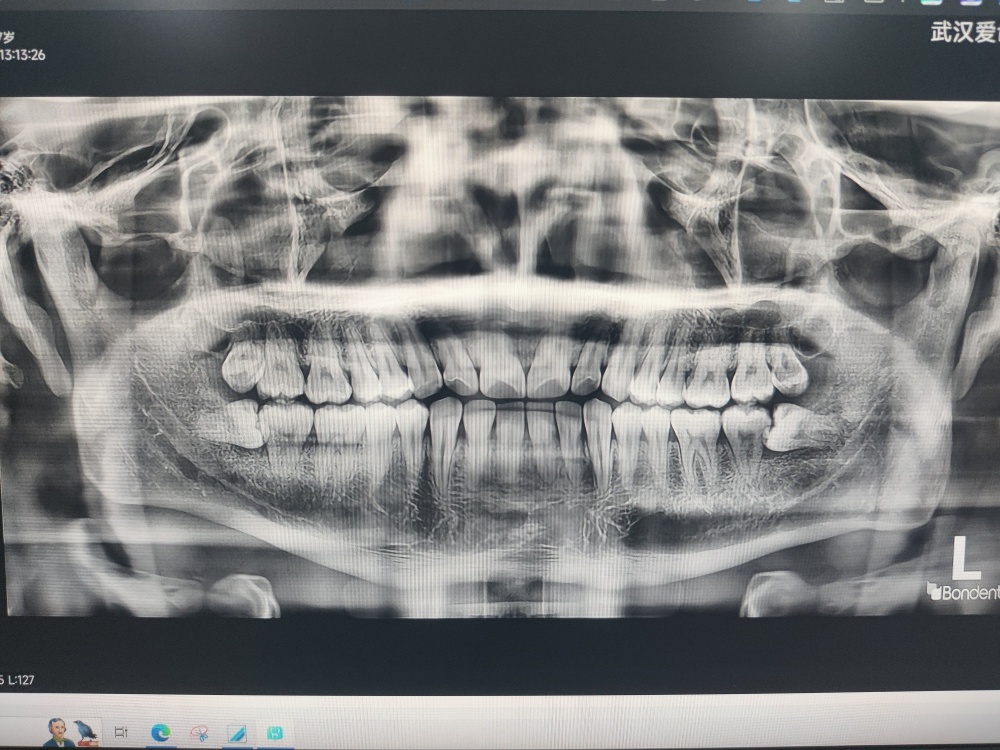

今天去爱齿尔口腔医院洗了个牙(美团黑金会员免费洗牙),顺便了解一下自己牙齿的健康状况,牙龈状态还不错,就是智齿问题有点烦,目前在预防智齿发炎,等钱包余额鼓鼓的再拔吧。我就担心有牙周炎最后牙龈萎缩,年纪轻轻牙齿就脱落了,就太惨了。还好我已经关注到牙齿健康的问题,还不算太晚。看别人牙龈萎缩最后牙齿掉没了,种牙就得20万,想想就可怕。而且食欲都受影响。吃啥,啥不香了!